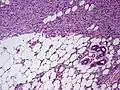

| Histopathological image of dermatofibrosarcoma protuberans. Local recurrence long after the first excision. H&E stain | |

Subcutaneous tissue infiltration (i.e. "honeycomb" growth pattern)

Subcutaneous tissue infiltration (i.e. "honeycomb" growth pattern) Monotonous, plexiform structure of tumour

Monotonous, plexiform structure of tumour DFSP formed both by fibroblastic and histiocytic elements

DFSP formed both by fibroblastic and histiocytic elements Hemosiderin deposits beneath the tumour

Hemosiderin deposits beneath the tumour_CD34.JPG.webp) Immunostain positive for CD34

Immunostain positive for CD34